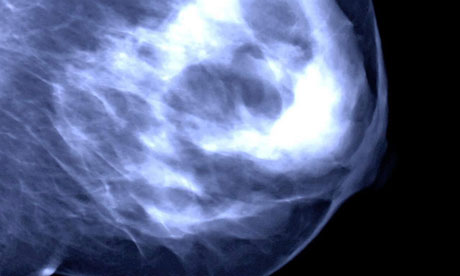

How many women have a faulty gene that increases their risk of breast cancer?

Only about one in 400 women in the UK carries the faulty version of either of the two genes, BRCA1 and BRCA2, both of which significantly increase the risk of breast or ovarian cancer. But, Wishart points out: "While they are incredibly rare they are also what we call high penetrance genes – that is, if you have one of these genes there's a very high chance that it will cause problems such as breast cancer."

Having the mutated version of either of those genes means a woman's risk of developing breast cancer can be up to 80% and as much as 50% of getting ovarian cancer. These are what are called someone's lifetime risk.

However, mutated BRCA genes cause only between 3% and 5% of all the 50,000 breast cancers a year that are diagnosed in the UK, or between 1,500 and 2,500 cases.